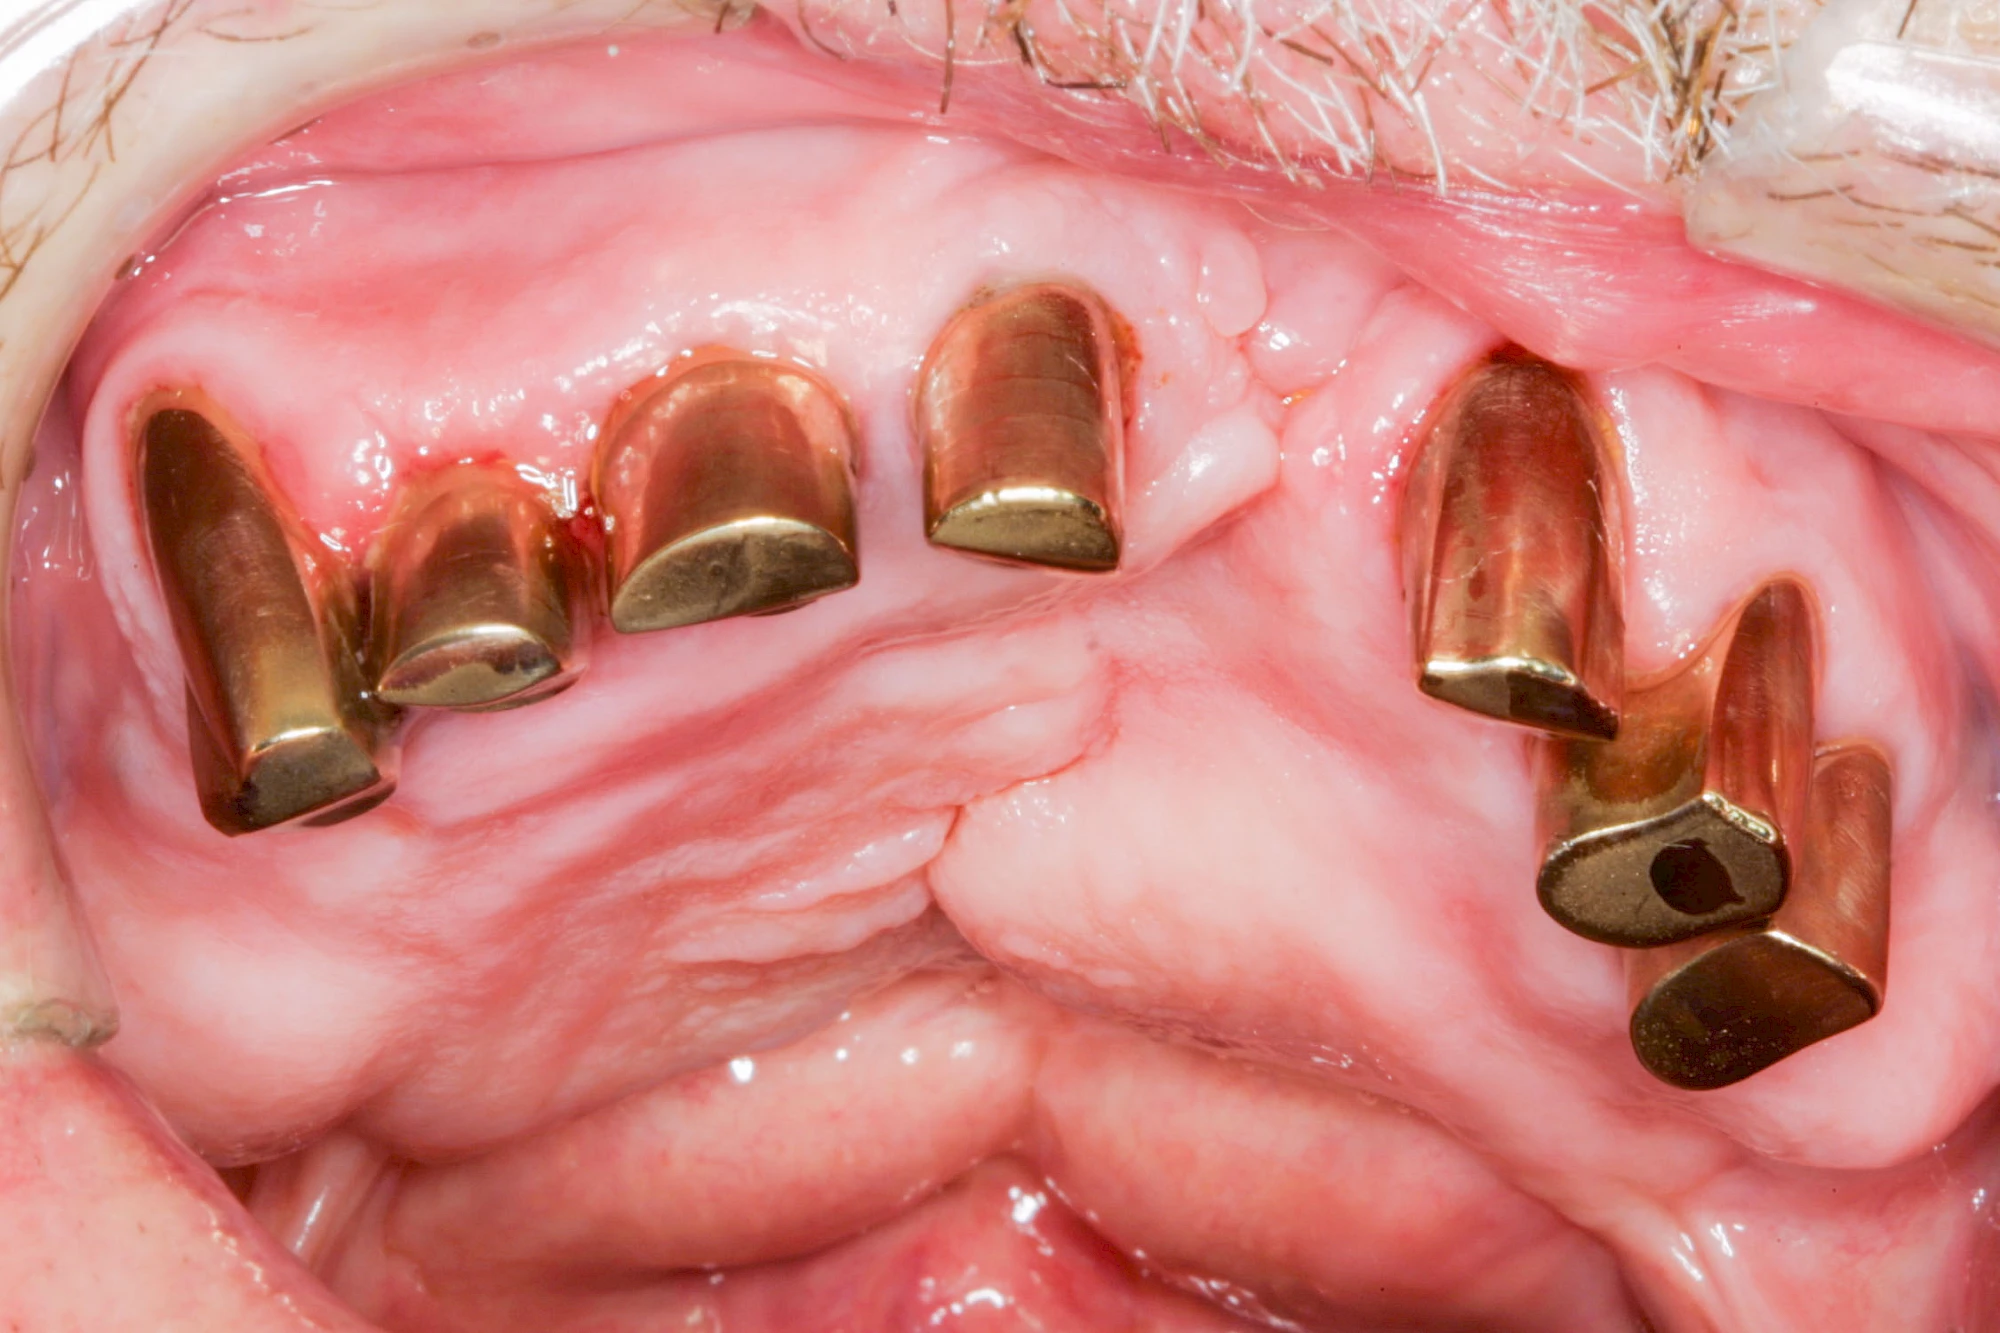

Gehen die Zähne verloren, baut häufig auch der Kieferknochen ab (Knochenschwund). Die Geschwindigkeit und das Ausmaß des Knochenschwundes ist von vielen Faktoren abhängig. Neben der genetischen Veranlagung spielen auch Überbelastungen in Folge, z. B. bei ständigem Knirschen oder Pressen, eine Rolle. Auch wenn Zahnprothesen Tag und Nacht getragen werden, kann die ständige Belastung der Schleimhäute und des Knochens den Knochenschwund beschleunigen.

In seltenen Fällen schwindet nur der Knochen, aber nicht die bedeckenden Schleimhäute. In diesen Fällen spricht man von einem sogenannten "Schlotterkamm".